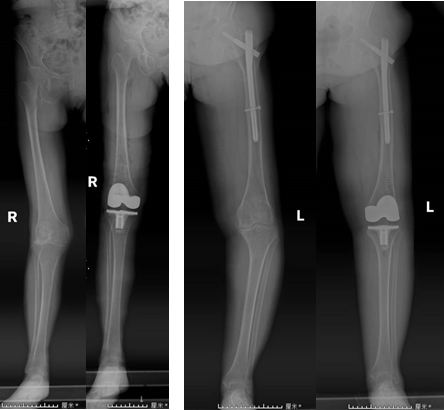

手術前后患者X線片對比

全膝關節手術定位系統(iKPAS)可用于初次或復雜全膝關節置換手術,在不開髓的情況下實現膝關節力線的定位,尤其針對股骨骨折內固定物未取出的情況,優勢更加明顯。